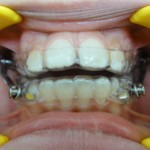

Vue de Face

L’appareil est fait d’un système de gouttières et d’activateurs : ce sont les bielles présentes de chaque côté.